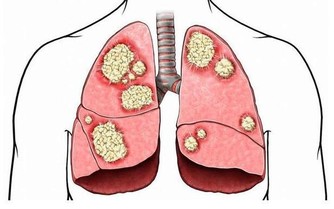

事實上,包括胃癌、宮頸癌、肝癌、肺癌等,常在晚期被發現。為什麼會發生這些?

此外,更可怕的是,許多類型的癌症正在迅速發展,並可以在短短幾個月內發展到晚期,擴散和轉移。

如果身體某一部位突然疼痛,持續一個多星期,應盡快查明原因。例如,長期腹痛是大腸癌的症狀;胸痛可能是肺癌引起的;骨痛可能是癌症轉移的症狀。這時,我們應該去醫院找醫生檢查一下。